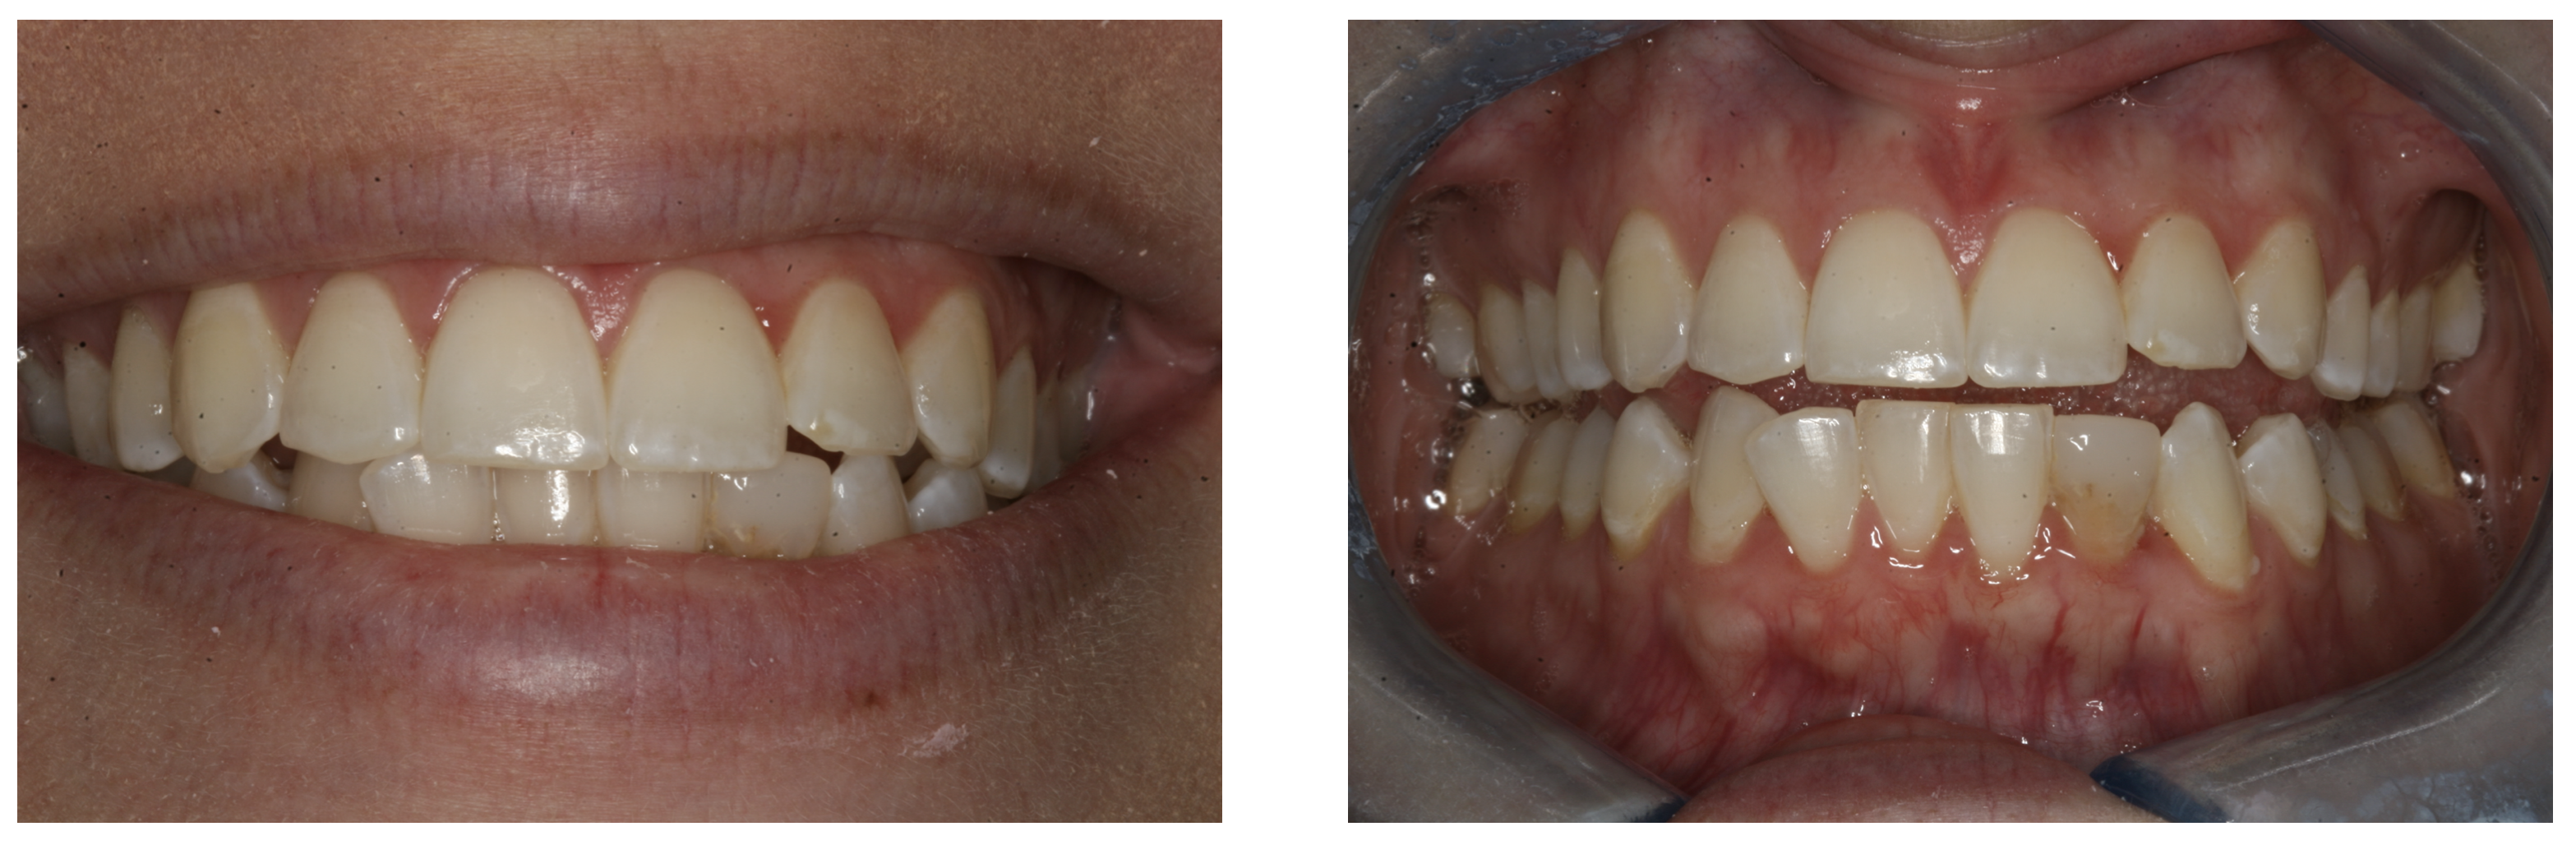

Figure 7 shows the day of delivery in a case in which a patient had undersized laterals compared to the rest of her teeth, so the practitioner added porcelain veneers on teeth Nos. 7 and 10. The practitioner did a prepless veneer employing a total etch technique and cemented with a universal.

Another patient presented with veneers approximately 15 years old, and the cement color had darkened over the years. The clinician applied four veneers from teeth Nos. 7 and 10 that resulted in excellent esthetics, proving the practicability of using a universal on anteriors.

In the next case, the practitioner used a zirconia crown to replace an e.max crown on tooth No. 23 that had brown staining/discoloration. The practitioner used a universal to place the zirconia crown.  Excellent gum tissue health also was a result.

Another patient presented with composite buildups on teeth Nos. 7 and 8, which were narrow and small. The clinician replaced them with zirconia crowns. No matter the substrate and type of restoration, a universal is indicated.